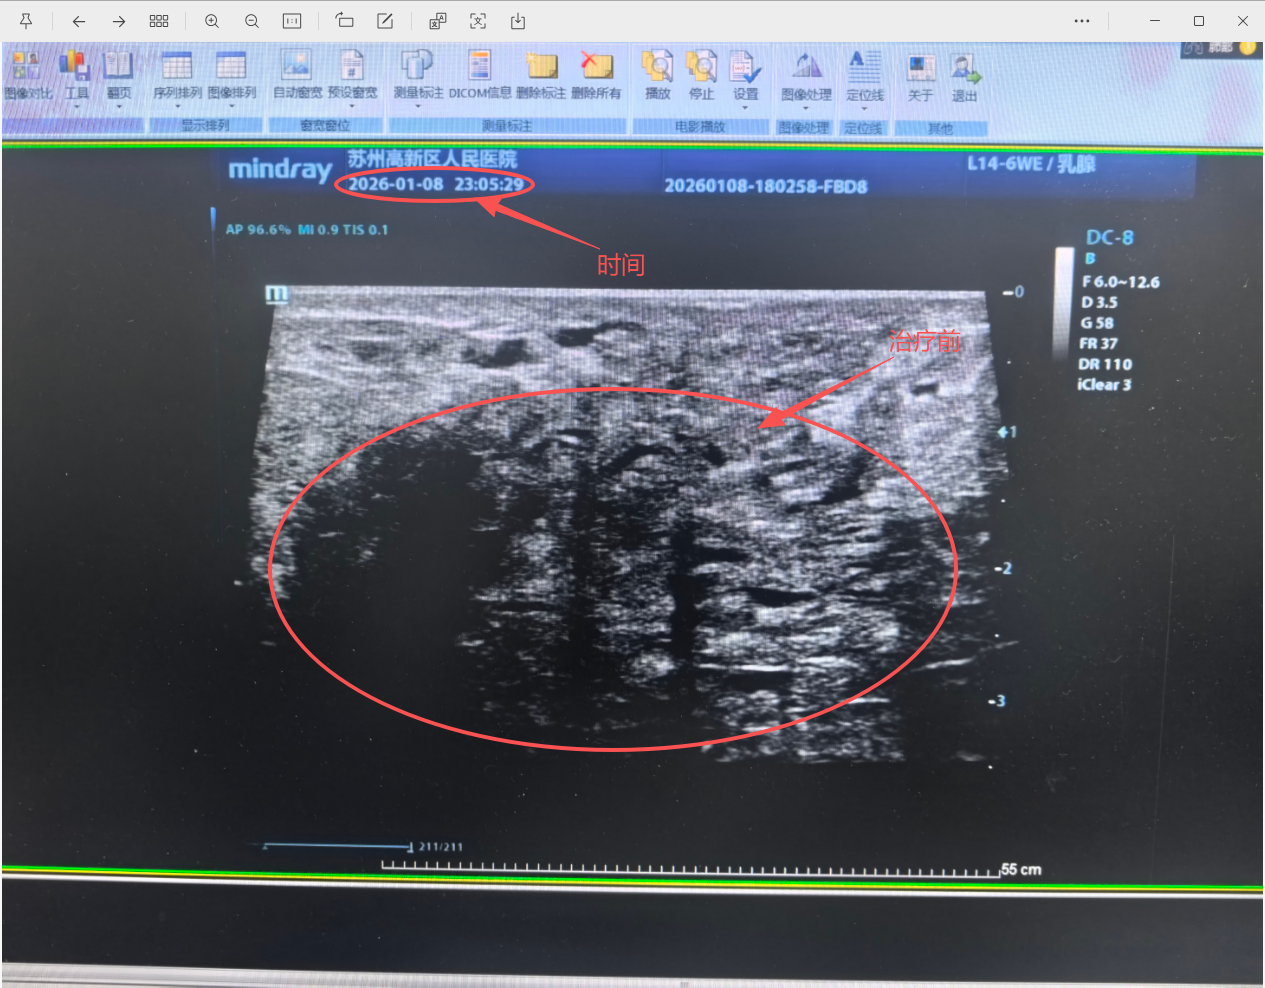

治疗前